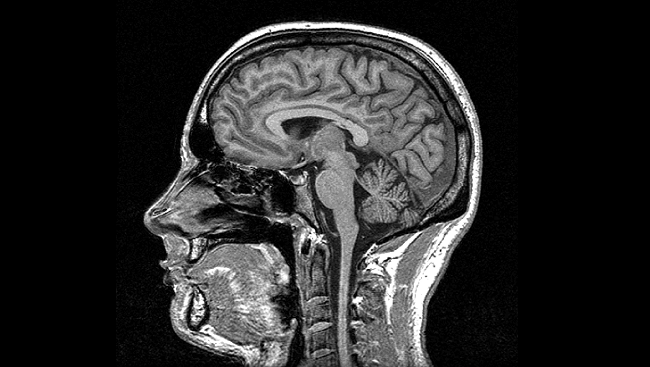

Magnetic Resonance Imaging (MRI)

- Magnetic resonance

- Some common isotopes (e.g., H) & complex molecules have a magnetic dipole

- Axes align with strong magnetic field

- When alignment perturbed by radio frequency (RF) pulse, speed of realignment varies by tissue

- Realignment emits RF signals

- How MRI works

- Types

- Structural

- Reveals tissue density/type differences

- Gray matter (neurons & dendrites & axons & glia) vs. white matter (mostly axons)